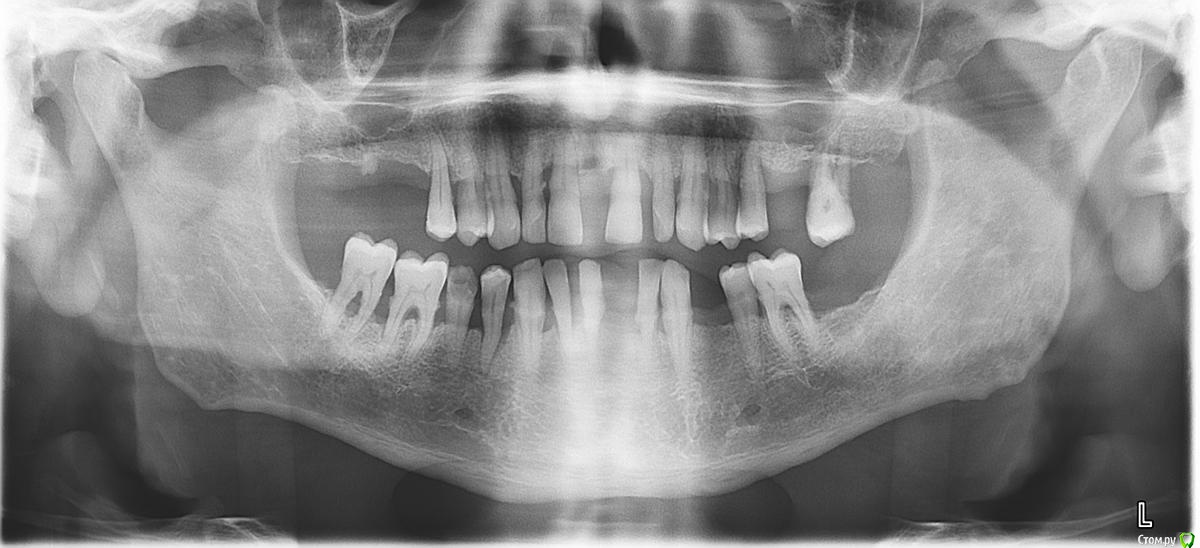

Orange1 Опубликовано 22 июля, 2017 Поделиться Опубликовано 22 июля, 2017 Коллеги всем доброго дня!назрел вопрос.Как быстро регенерирует мембрана шнайдера после перфораций (до 1.5 cм)?Через какое время идете на повторный синус? P.s. из своего кейса:Двухсторонний открытый синус: 1ая сторона без вопросов. 2ая:при доступе получил перфу которая увеличилась,но это пол беды -в пазухе уже обнаружил образование с густым белым содержимым, смутило-аспирировал промылся на окно мембрану уложил к лору направляю.там все начинается с септопластики и т.д. Зубы удалены.срезы залью позже. Поделитесь подобным опытом коллеги.Всем спасибо! Ссылка на комментарий